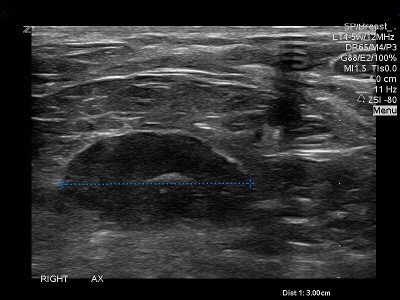

👉When a lymph node is completely replaced with metastatic cancer, it will be rounded, hypoechoic, and the hilum will be completely obliterated. (Image).

👉Before the node reaches the stage of complete replacement, it can have an asymmetric, thickened cortex, with an eccentric hilum (Image).